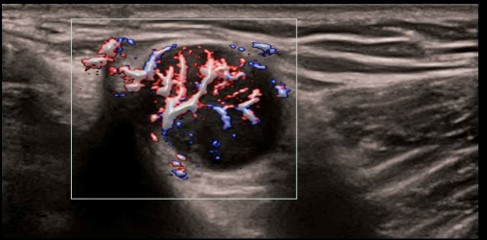

CPP: Vhodné na diagnostiku extrémne jemných prietokov (napr. reumatoidná artritída). Automatická štatistika percentuálneho podielu farebných pixelov v rámci vyšetrovanej oblasti.

CPP: Vhodné na diagnostiku extrémne jemných prietokov (napr. reumatoidná artritída). Automatická štatistika percentuálneho podielu farebných pixelov v rámci vyšetrovanej oblasti.

CPP: Vhodné na diagnostiku extrémne jemných prietokov (napr. reumatoidná artritída). Automatická štatistika percentuálneho podielu farebných pixelov v rámci vyšetrovanej oblasti.